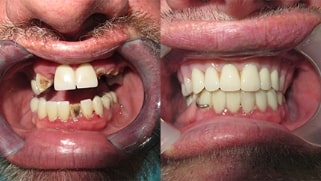

Dental Implants in Mexico Reviews

Hesitating about the quality of our treatments or the credentials of our specialists?

Watch some of our patients’ testimonials Before and After their implants treatment in Tijuana.

Implant Art

Tijuana

At X Dentistry, our specialists are real dental artisans.

Through a detailed and careful process and using state-of-

the-art materials and technologies, we can offer you

naturally aesthetic results that will exceed your

expectations!

Get ready to show off an impeccable and renewed smile

that will improve your ability to eat, speak and socialize.

Feel self-confident and increase your self-esteem thanks to

our implants and mini dental implants in Tijuana Mexico!